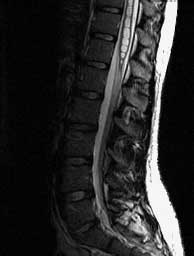

FSE T2 sagittals

Septated cavity with CSF signal extending form C3 to the conus. Peglike cerebellar tonsils herniated well below the foramen magnum.